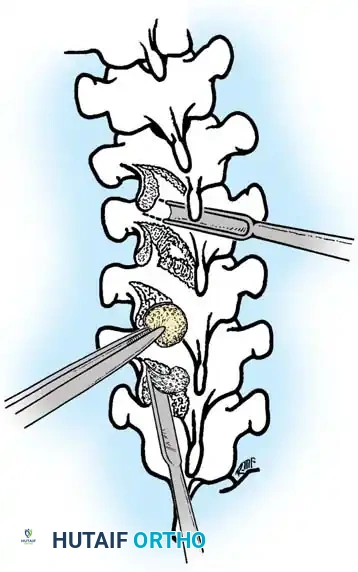

The Moe Technique (Lumbar Spine)

In the lumbar spine, the facet joints are oriented in a more sagittal plane, necessitating a modified approach.

Fig. 38-27: The Moe technique adapted for lumbar facet fusion, addressing the sagittal orientation of the joints.

- Utilize a small osteotome or a needle-nose rongeur to resect the adjoining joint surfaces.

- This creates a distinct rectangular defect within the sagittally oriented joint space.

- Pack this defect forcefully with cancellous bone graft.

- Proceed to decorticate the entire exposed posterior elements (laminae and transverse processes) using Cobb gouges, always directing force away from the spinal canal.